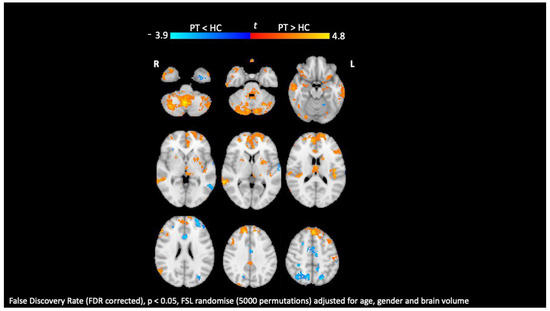

- Kolasa, M.; Hakulinen, U.; Brander, A.; Hagman, S.; Dastidar, P.; Elovaara, I.; Sumelahti, M. Diffusion tensor imaging and disability progression in multiple sclerosis: A 4-year follow-up study. Brain Behav. 2019, 9, e01194. [Google Scholar] [CrossRef] [PubMed]

- Lopez-Soley, E.; Martinez-Heras, E.; Solana, E.; Solanes, A.; Radua, J.; Vivo, F.; Prados, F.; Sepulveda, M.; Cabrera-Maqueda, J.M.; Fonseca, E.; et al. Diffusion tensor imaging metrics associated with future disability in multiple sclerosis. Sci. Rep. 2023, 13, 3565. [Google Scholar] [CrossRef] [PubMed]